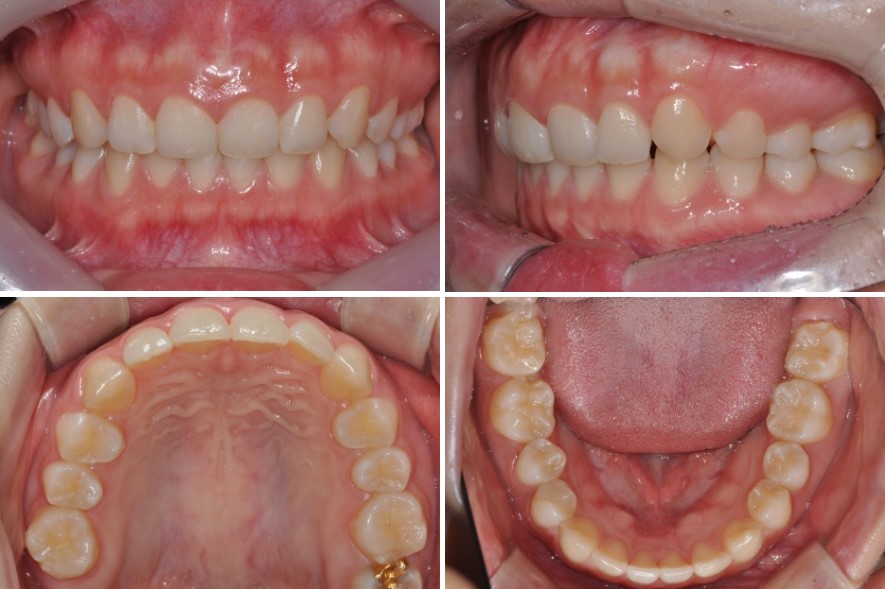

케이스 소개: 20대 여성, 비대칭과 거미스마일로 내원

20대 여성분이 웃을 때 잇몸이 많이 보이는 거미스마일을 해결하고 싶다며 내원하셨습니다.

얼굴을 정면에서 보면 약간의 비대칭이 있기는 하지만,

입술을 다문 모습만 놓고 보면 크게 눈에 띄는 문제는 없어 보였습니다.

구강 내 상태를 살펴보면 치열 자체는 비교적 가지런한 편이었으나,

비대칭을 동반한 2급 부정교합(위턱이 상대적으로 앞으로 있는 교합) 양상을 보이고 있었습니다.

겉보기에는 치아 배열이 크게 삐뚤지 않아 단순히 “정리만 하면 될 것 같다”고 생각하기 쉽지만, 실제로는 교합 관계에 문제가 있는 상태였습니다.

가장 큰 고민이었던 부분은 역시 웃을 때 심하게 드러나는 잇몸, 즉 거미스마일이었습니다.